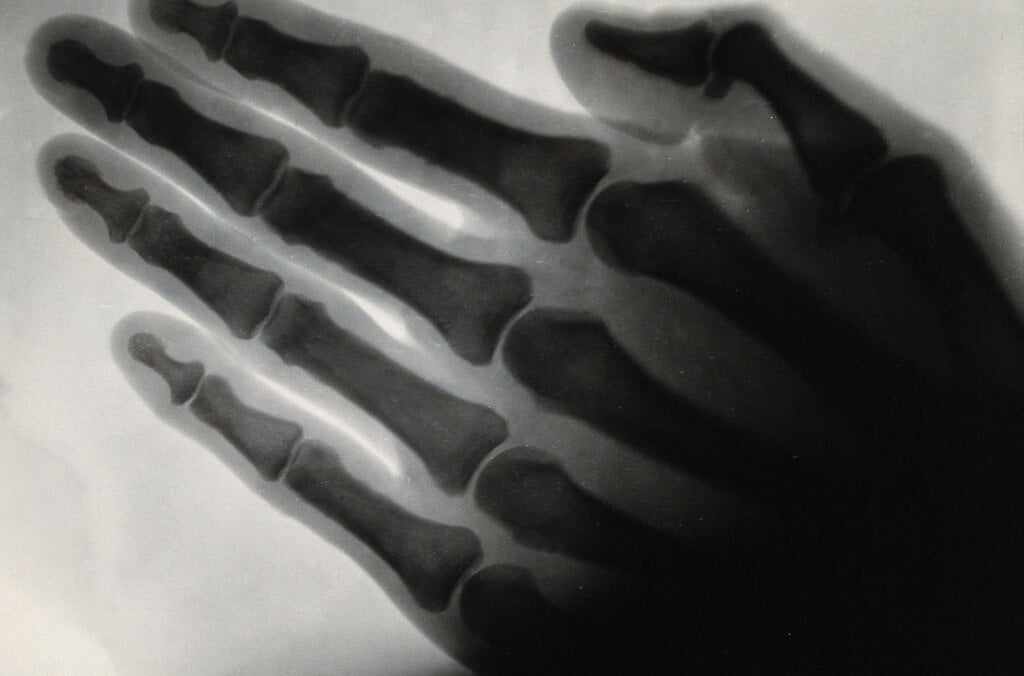

Nobel Prize in Physics 1901

The very first Nobel Prize in Physics was awarded to Wilhelm Röntgen for his discovery of X-rays. They are still used to diagnose bone fractures, locate embedded bullets and more.

X-rays

Credit: Wellcome Collection.